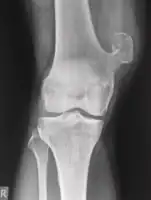

Medical imaging usually shows a well-defined wide-based bony growth on the surface of bone.[5] It can be pedunculated and irregular, giving it a "bizarre" appearance, and is not connected to underlying bone.[2]

X-ray hand, BPOP 2nd metacarpal

X-ray hand, BPOP 2nd metacarpal (side view)